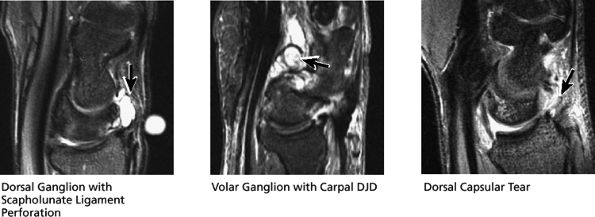

FIGURE 10.33 ● Normal sagittal anatomy. (A) The first carpometacarpal joint, visualized at the top of the field of view on sagittal images, is a common location for degenerative arthrosis. (B) Similar to the hamate, the trapezium also has a “hook,” although it is smaller and is rarely fractured. (C) An anteriorly tipped (or “flexed”) scaphoid is a sign of carpal instability, often associated with scapholunate ligament tears or scaphoid fractures. (D) DISI is suggested when the capitate lunate angle exceeds 30°. When DISI is present, the scapholunate ligament is evaluated for associated tears. (E) Sagittal images afford another opportunity to examine the hook of the hamate for fractures. (F) Triquetral fractures usually occur when the dorsal aspect of the triquetrum is avulsed by the radiotriquetral ligament. Similar to the lateral view on plain films, sagittal images demonstrate the dorsal triquetral avulsion fracture fragment. (G) Sagittal images through the abductor pollicis longus and extensor pollicis brevis tendon afford additional opportunities to identify and characterize the findings of de Quervain's stenosing tenosynovitis. (H) Occasionally, focal prominence of tortuous veins and arteries about the wrist can mimic ganglion cysts on sagittal fluid-sensitive sequences. These vessels can be distinguished from ganglions by viewing successive images and visualizing continuity of the vascular structures. (I) Tears and sprains of the dorsal and volar extrinsic capsular ligaments are optimally visualized in the sagittal plane. (J) The longitudinal extent and length of median nerve involvement in median neuritis can be measured and characterized in the sagittal plane. (K) Near its radial attachment, the triangular fibrocartilage fans out to a broad, bowtie-shaped structure, resembling the appearance of the meniscus on sagittal images of the knee. (L) Near its ulnar attachment, the triangular fibrocartilage is visualized as a short, narrow band of hypointense cartilage that represents the convergence of the dorsal and volar radial ulnar ligaments at the apex of the triangular TFC.

FIGURE 10.52 GANGLION CYSTS AND DORSAL CAPSULE.